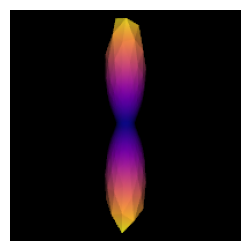

One simple way to estimate the fiber response function is to look for regions of the brain where it is known that there are single coherent fiber populations. For example, if we use a ROI at the center of the brain, we will find single fibers from the corpus callosum. The auto_response_ssst function will calculate FA for a cuboid ROI of radii equal to roi_radii in the center of the volume and return the response function estimated in that region for the voxels with FA higher than 0.7.

To double-check that we have a good response function we can visualize the response function’s ODF:

scene = window.Scene()

evals = response[0]

evecs = np.array([[0, 1, 0], [0, 0, 1], [1, 0, 0]]).T

response_odf = single_tensor_odf(default_sphere.vertices, evals, evecs)

# transform our data from 1D to 4D

response_odf = response_odf[None, None, None, :]

response_actor = actor.odf_slicer(response_odf, sphere=default_sphere,

colormap='plasma')

scene.add(response_actor)

csd_response = window.snapshot(

scene, fname=os.path.join(os.getcwd(), 'csd_response.png'), size=(200, 200),

offscreen=True)

fig, axes = plt.subplots(figsize=(3,3))

axes.imshow(csd_response, cmap="plasma")

axes.axis("off")

plt.show()